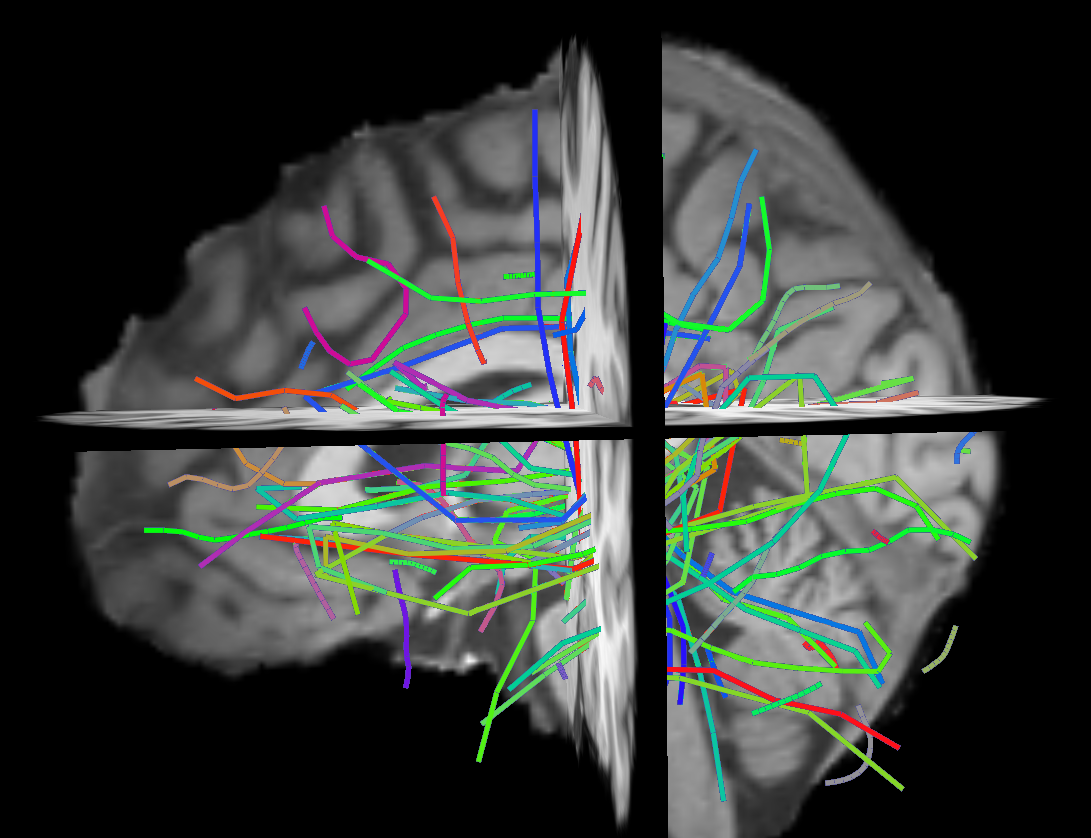

Deterministic tractography algorithms [8] can reconstruct white matter fiber tracts as a set of streamlines, also known as tracks, from diffusion Magnetic Resonance Imaging (dMRI) [2] data. A streamline is a mathematical approximation of thousands of neuronal axons expressing anatomical connectivity between different areas of the brain, see Figure 1. Recently there has been an increase of attention in analysing dMRI/tractography data by means of machine learning and pattern recognition methods, e.g. [14, 13]. These methods often require the data to lie in a vectorial space, which is not the case for streamlines. Streamlines are polylines in 333D space and have different lengths and numbers of points. The goal of this work is to investigate the features and limits of a specific Euclidean embedding, i.e. the dissimilarity representation, that was recently applied to the analysis of tractography data [9].

Refer to caption

Figure 1: A set of 100100100 streamlines, i.e. an example of prototypes, from a full tractography

We estimated the dissimilarity representation over tractography data from dMRI recordings of the MRI facility at the MRC Cognition and Brain Sciences Unit, Cambridge UK. The dataset consisted of 121212 healthy subjects; 101101101 (+11+1, i.e. b=0𝑏0b=0) gradients; b𝑏b-values from 0 to 4000; voxel size: 2.5×2.5×2.5mm32.52.52.5𝑚superscript𝑚32.5\times 2.5\times 2.5mm^{3}. In order to get the tractography we computed the single tensor reconstruction (DTI) and created the streamlines using EuDX, a deterministic tracking algorithm [5] from the DiPy library 444http://www.dipy.org. We obtained two tractographies using 104superscript10410^{4} and 3×1063superscript1063\times 10^{6} random seed respectively. The first tractography consisted of approximately 103superscript10310^{3} streamlines and the second one of 3×1053superscript1053\times 10^{5} streamlines. An example of a set of prototypes from the largest tractography is shown in Figure 1.